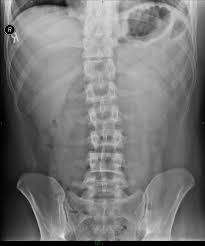

Az alábbi képeket a neten találtam, onnan másoltam ide, nem általam ismert konkrét esetek!

RTG képet már sokunk látott, de azért ide teszek kettőt. A bal oldalin egy lumbális><háti alsó szakasz látható (jól látszik a görbület) és egy medence felvétel (feltehetően a jobb csípőizület kopásával).

Íme: